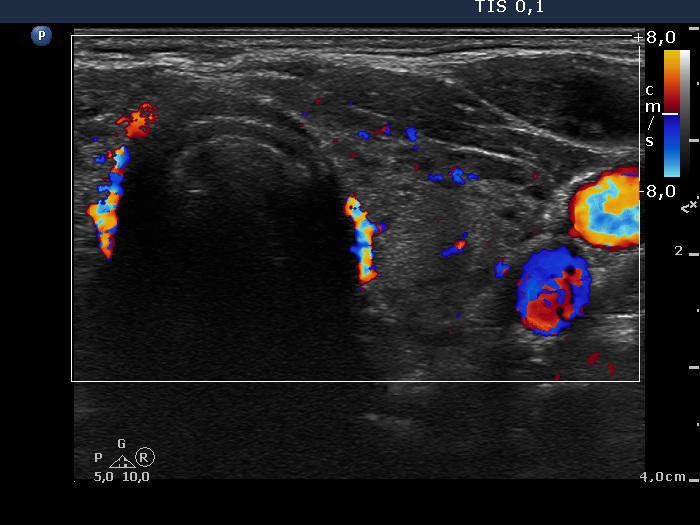

Right lobe, longitudinal scan

Left lobe, transverse scan, color Doppler mode. The vascularization is average.